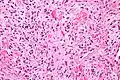

Solitary fibrous tumor - high magnification. H&E stain.

Solitary fibrous tumor - high magnification. H&E stain.